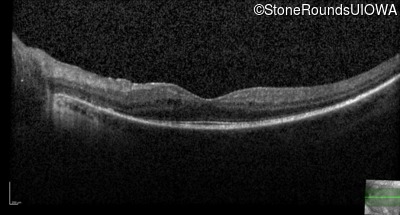

OCT Stack

20/32

20/32 -1

20/30 -2

20/32 -2

20/40

20/25 sc